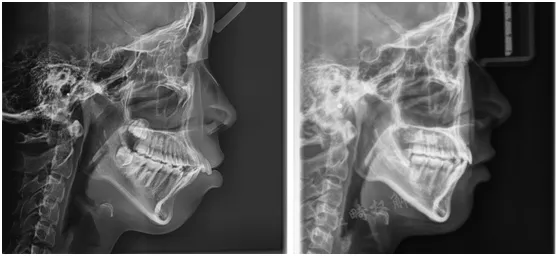

1、头颅侧位片解剖结构描绘及头影测量常用定点介绍

2、基础X线头影测量分析定点

3、X线头影测量画线

4、X线头影测量常用指标

5、X线头影测量分析

6、学员实操 头侧描记法

7、头影测量个性化诊断及制定诊疗计划

8、常见头影测量项目及临床意义精讲